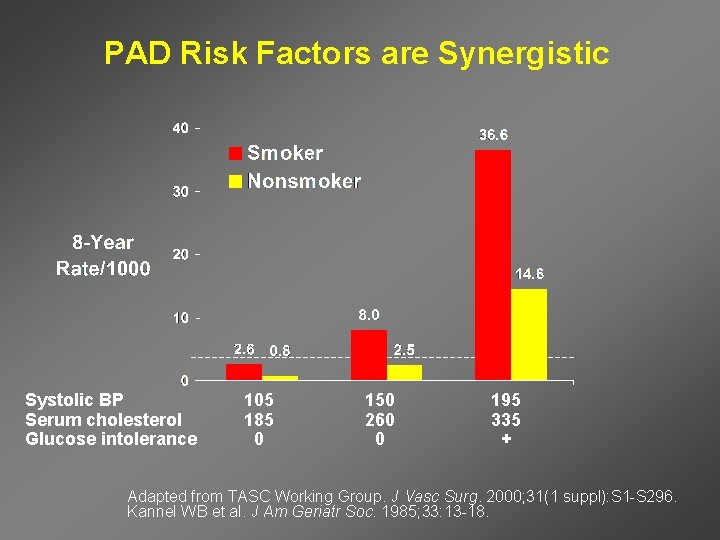

PAD Risk Factors are Synergistic Systolic BP Serum cholesterol Glucose intolerance 105 185 0 150 260 0 195 335 + Adapted from TASC Working Group. J Vasc Surg. 2000; 31(1 suppl): S 1 -S 296. Kannel WB et al. J Am Geriatr Soc. 1985; 33: 13 -18.